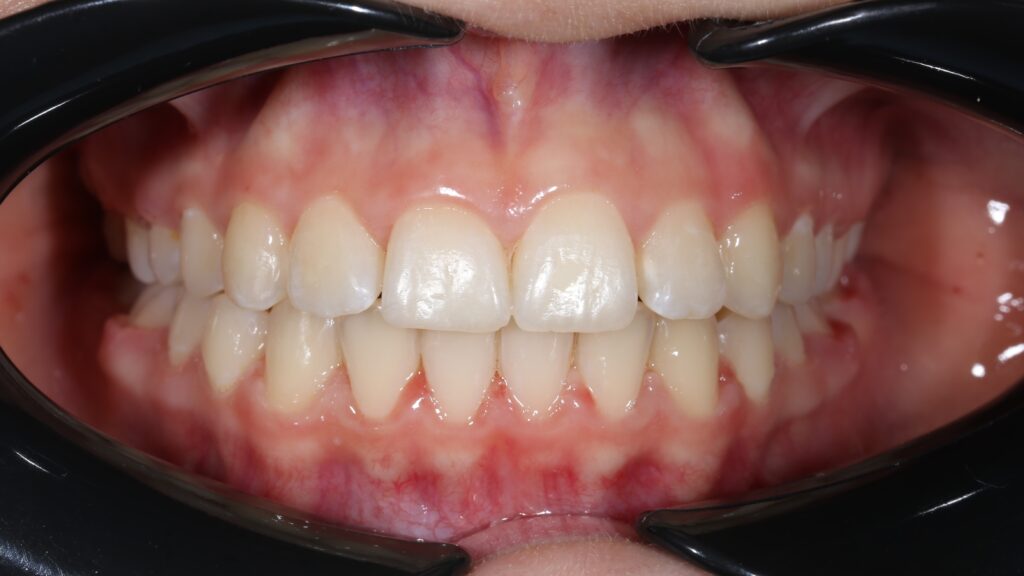

Результат

Была установлена брекет-система Damon Q.

Стоимость установки брекет-системы на обе челюсти (без стоимости коррекций): 1650 USD (цена указана ориентировочно по курсу НБРБ на день оплаты)

пациент после ортодонтического лечения